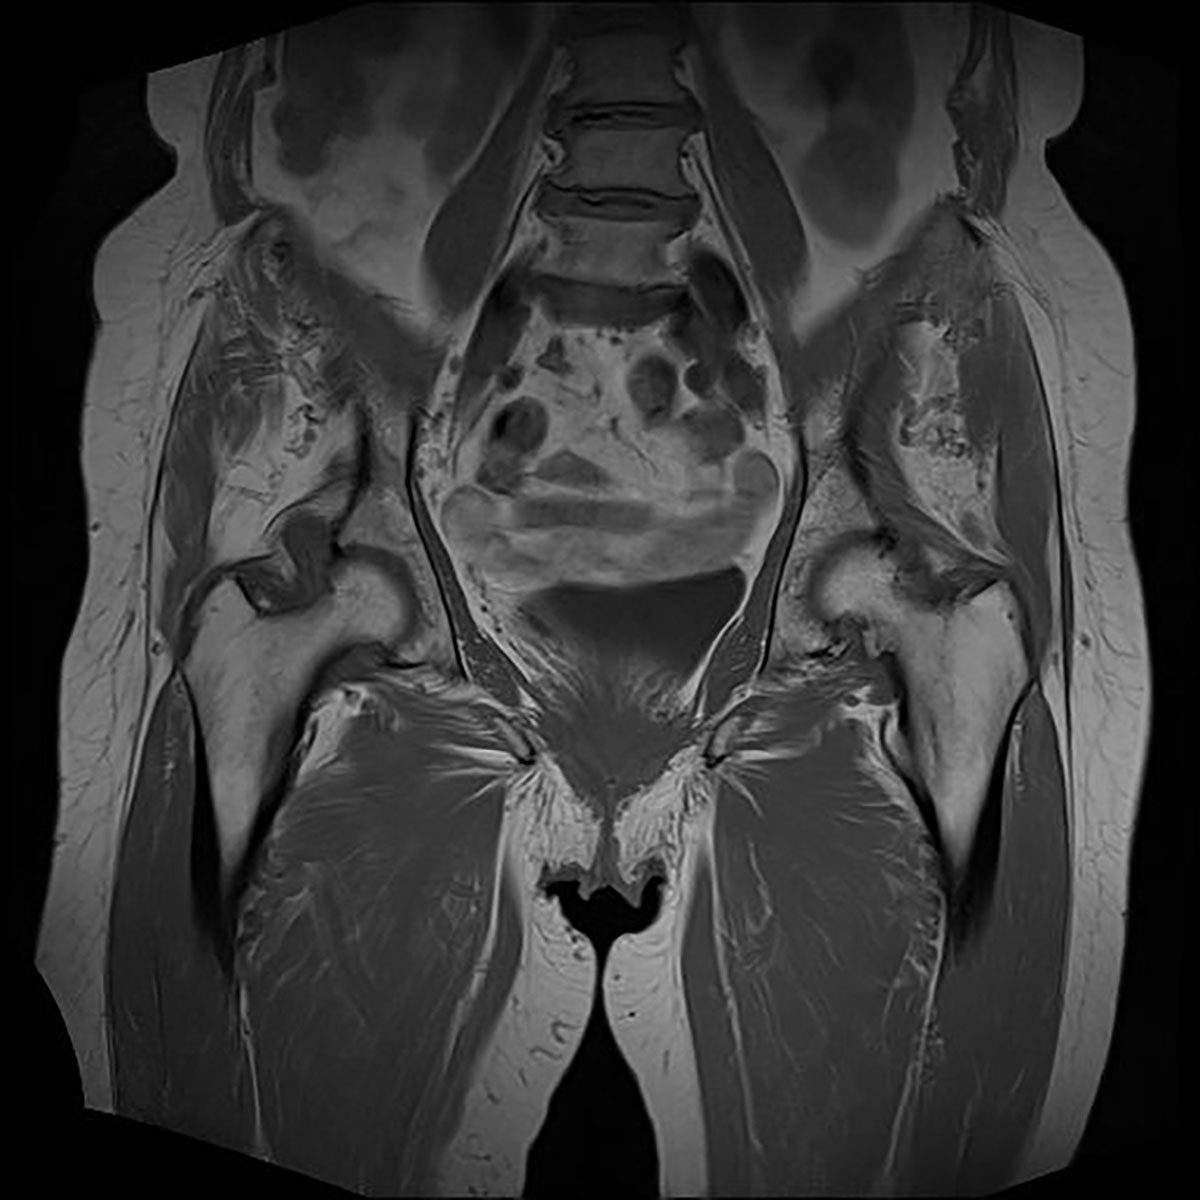

Neben einer typischen Anamnese und klinischen Untersuchung stellt die Bildgebung das entscheidende diagnostische Mittel zum Nachweis einer glutealen Insuffizienz dar. Konventionelle Röntgenbilder (Hüftübersichtsaufnahme a.-p., axiale Projektion des proximalen Femurs, ggf. Faux-Profilaufnahme) dienen zum Ausschluss ossärer Differentialdiagnosen. Bei einliegender Hüft-TEP muss auf mechanische Ursachen wie Lockerung und Komponentenfehlpositionierungen (Drehzentrum der Pfanne, Femur-Offset, Komponentengröße) geachtet werden. Bei nativem Gelenk können peritrochantäre Sehnenansatzverkalkungen oder osteophytäre Ausziehungen als Ausdruck degenerativer Veränderungen erkannt werden. Sonographisch bietet sich die Möglichkeit, ansatznahe Rupturen zu beurteilen, die Sensitivität wird vereinzelt als gut beschrieben. Als Goldstandard gilt die MRT des Beckens. Hierbei gelingt es, durch Wahl geeigneter Sequenzen und Schichtungen Tendinopathien und Rupturen hoch sensitiv nachzuweisen. Bei einliegender Hüft-TEP sind zur genauen Beurteilung der Glutealmuskulatur artefaktreduzierte Sequenzen (z. B. MARS) nötig.